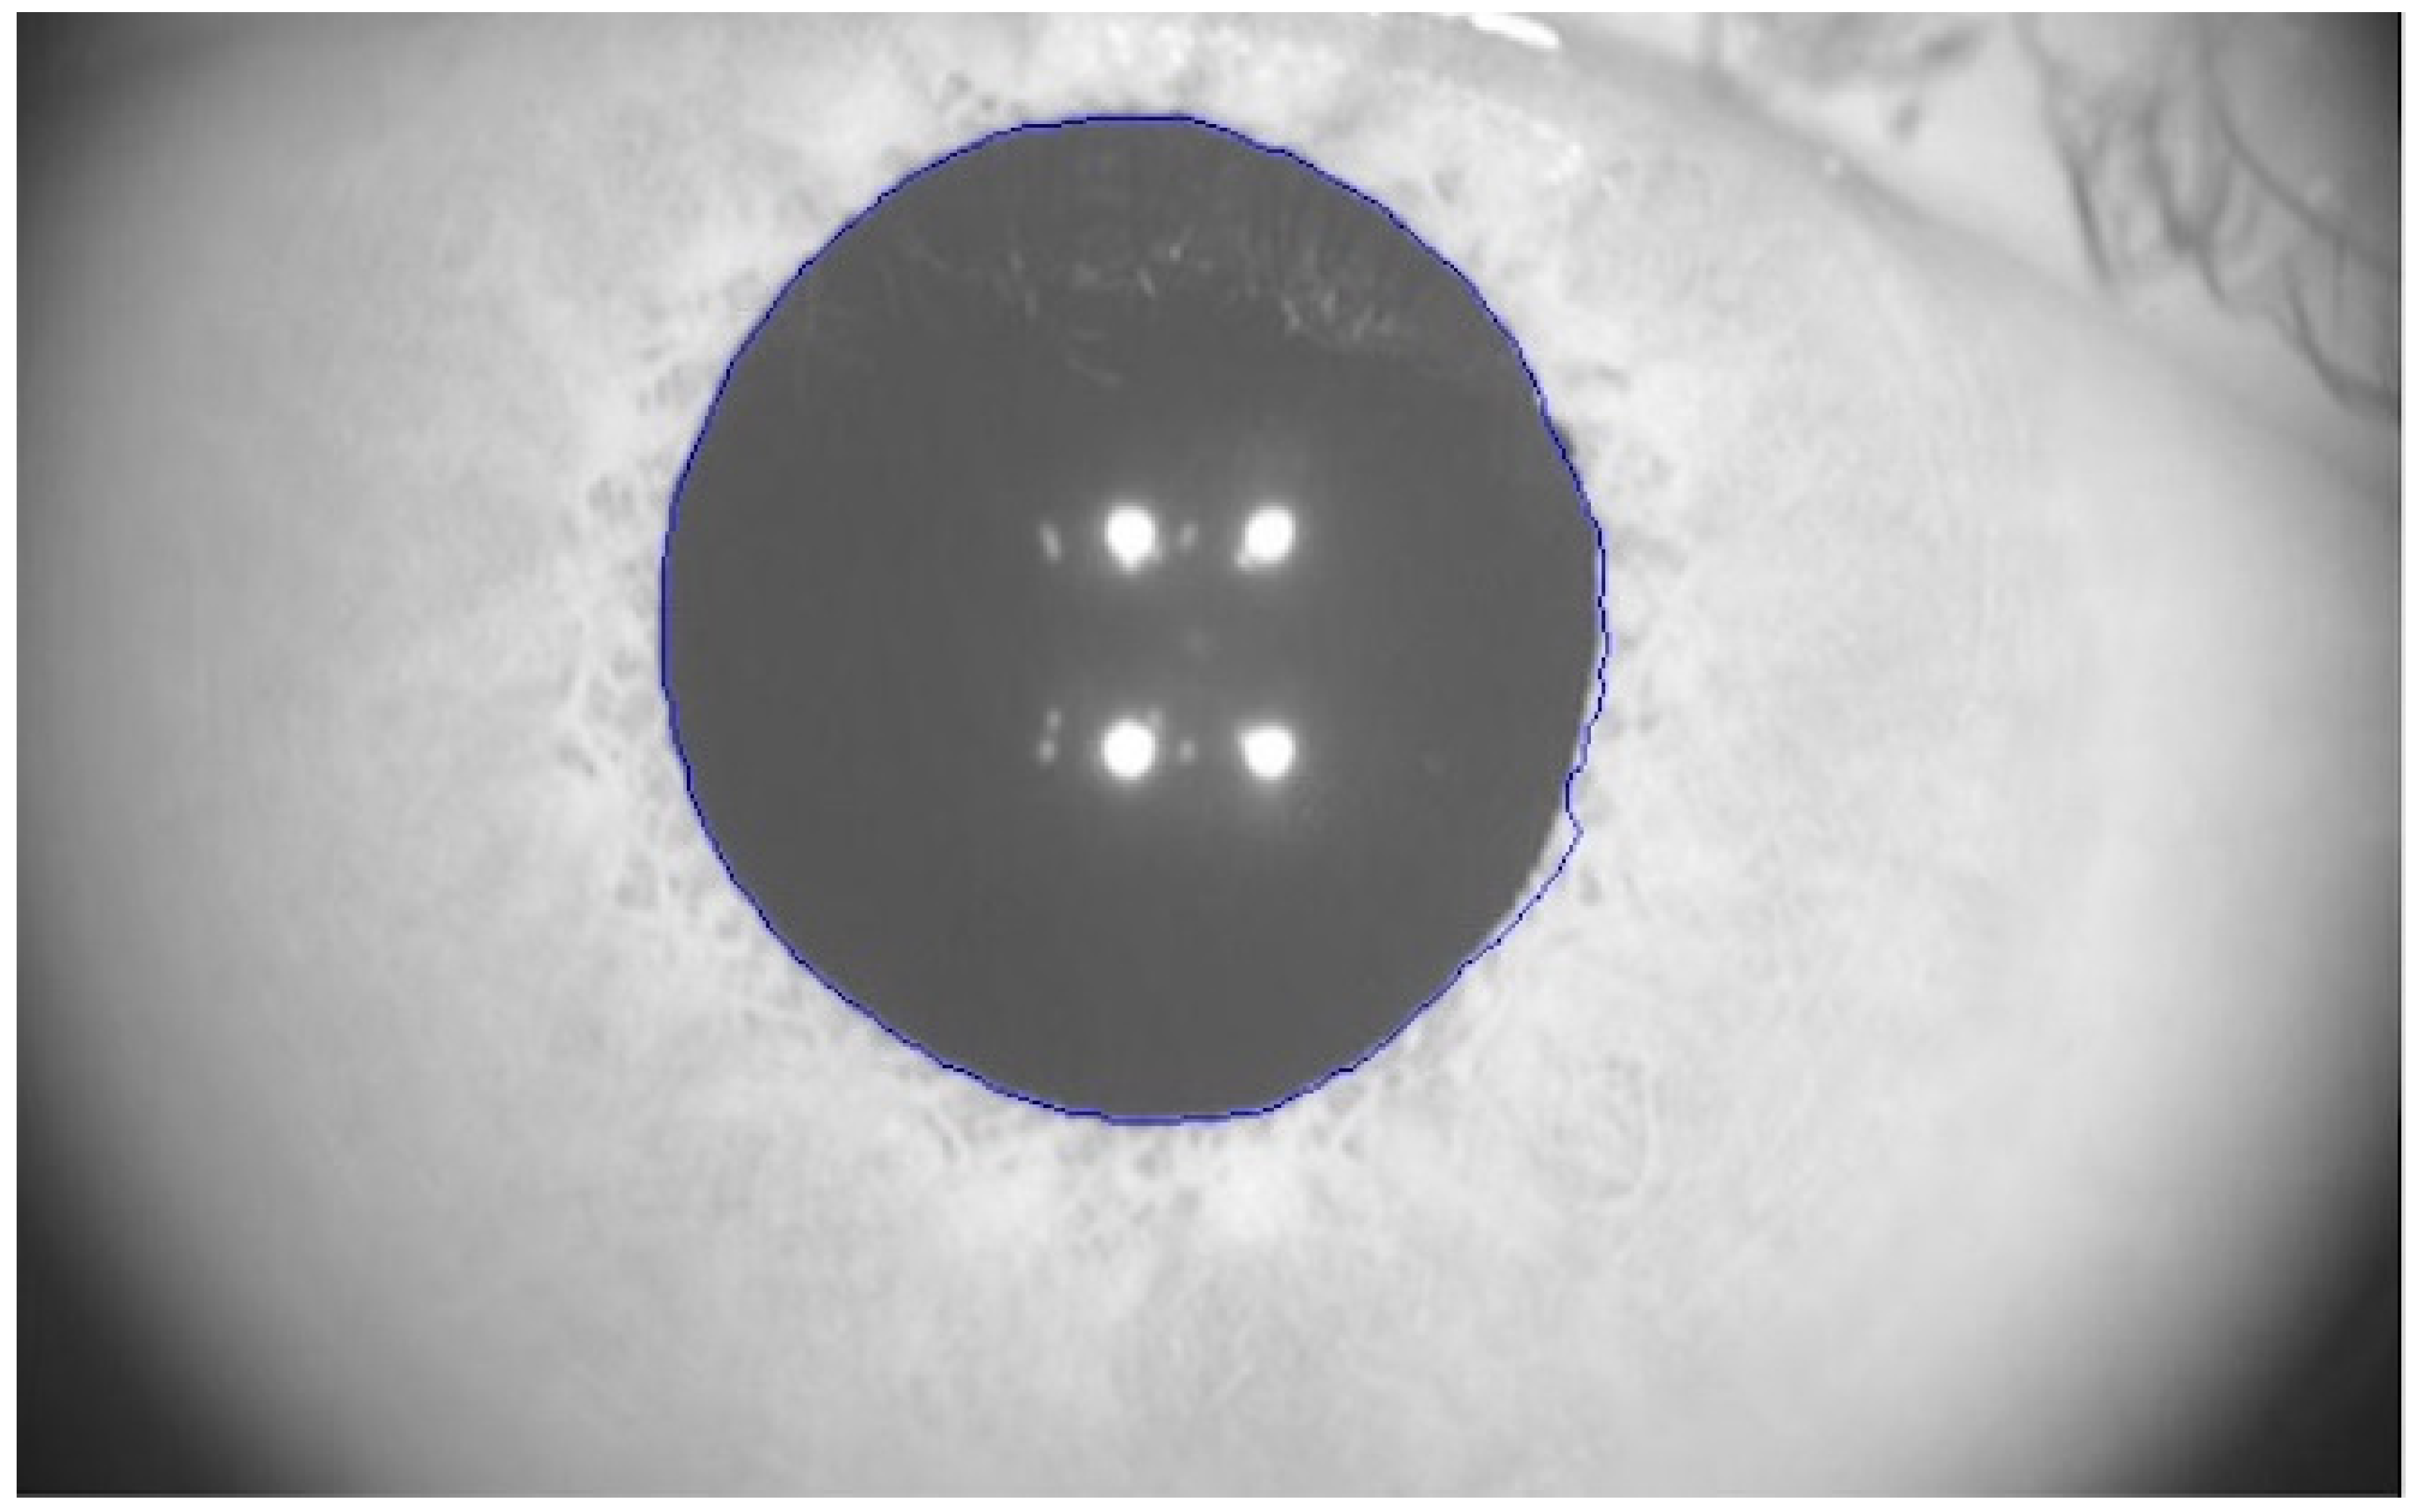

2.2. Pupilometer

Pupillary parameters were recorded with a module integrated into the MYAH topographer (Topcon EU, Tokyo, Japan). This module analyzes dynamic pupillometry with controlled light conditions using a central fixation LED and 2 white light LEDs for the photopic phase (1100 mcd). Pupillometric variation is monitored by four infra-red LEDs (940 nm). The total test time was 16 s: 2.5 s under low-medium lighting conditions (mesopic), 2.5 s under medium-high lighting conditions (photopic), and 11 s under low lighting conditions (scotopic). Unfortunately, the specific values for light intensity in cd/m2 for every illumination level were not provided by the manufacturer. Pupillary response is analyzed measuring the size of the pupil over time. This software automatically outlined the pupillary contours of the participants on the images, as exemplified in Figure 1 (blue line). The precision of the measure was ±0.05 mm.

Figure 1. Real image taken by MYAH topographer with the pupillometry module. The pupillary diameter is automatically detected and outlined in blue.